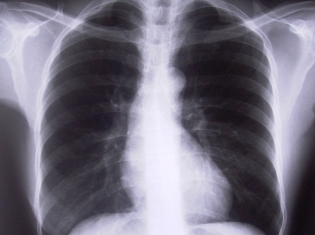

COPD is a group of diseases, including emphysema and chronic bronchitis, that involve difficulties with breathing and airflow. According to the Centers for Disease Control and Prevention (CDC), tobacco smoke is a key factor in COPD, but other factors like air pollutants, genetics and respiratory infections can be involved.